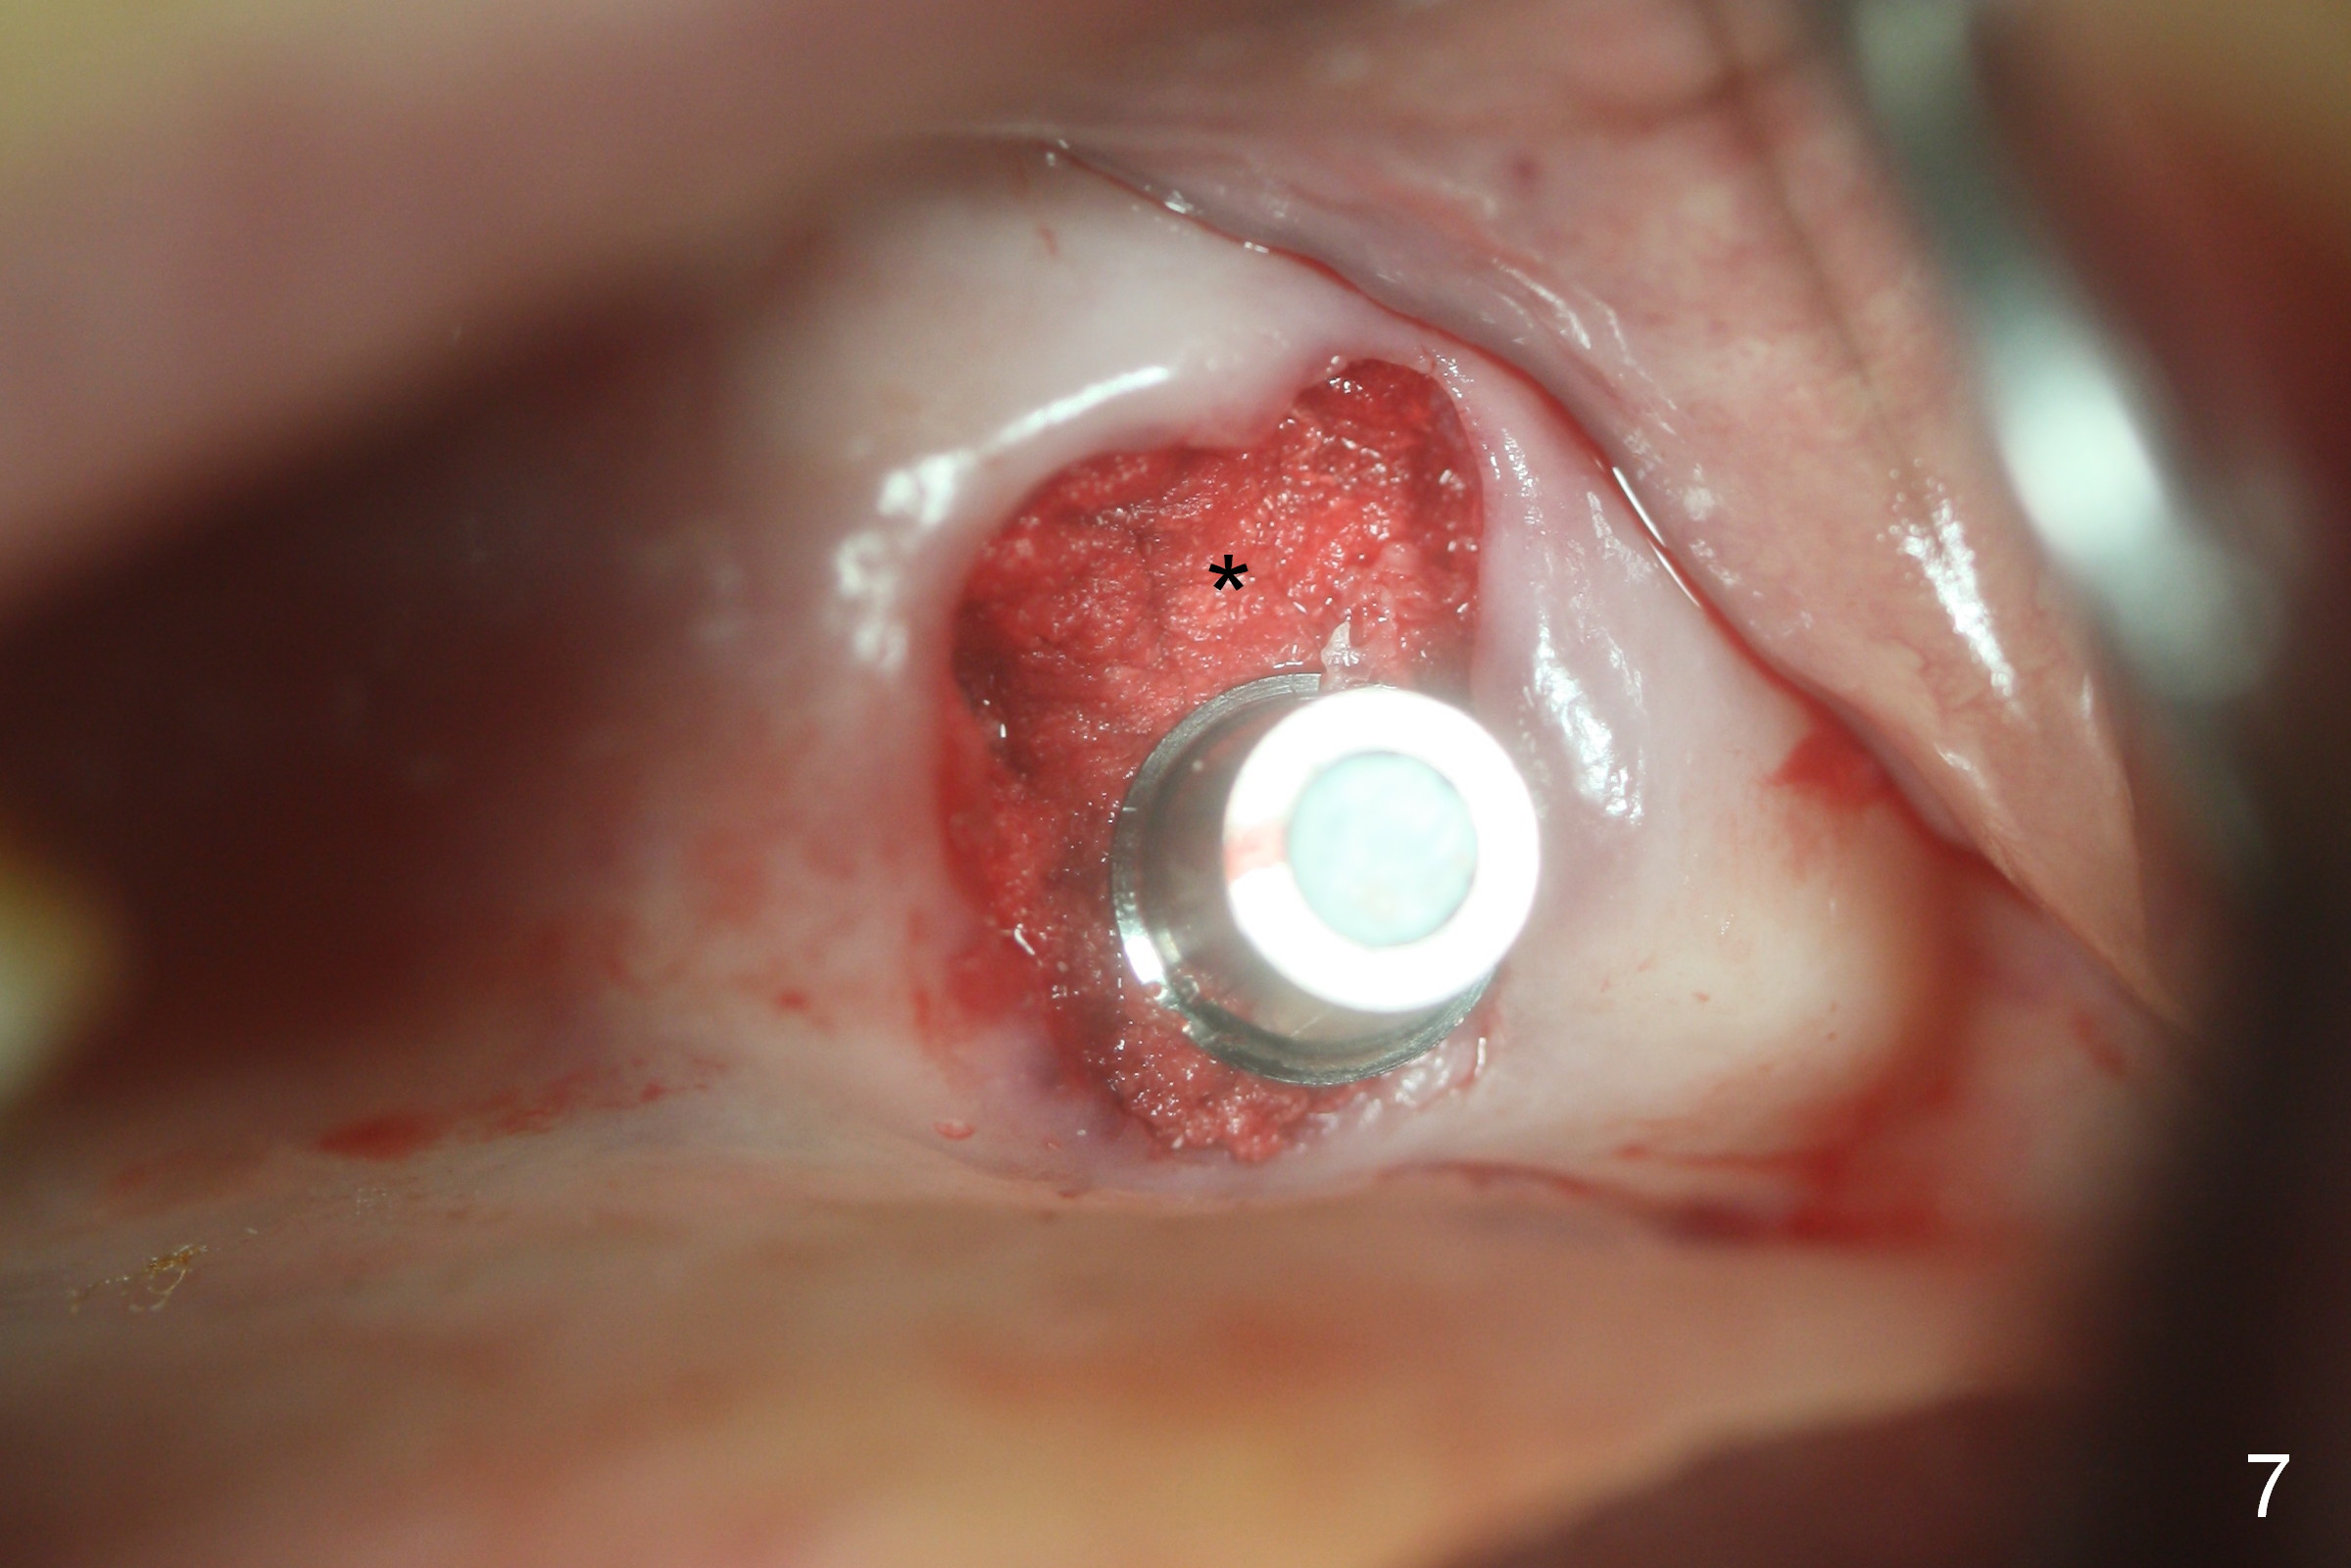

Fig.1,2 show the close relationship of the upper flipper and the residual roots at #15.  Atraumatic extraction using periotomes and surgical sectioning still results in perforation of the mesiobuccal socket (Fig.3 >).  The distobuccal one is shallow, while the septum is small.  It appears that the palatal (Fig.3 P) socket is the most ideal recipient site for the immediate implant and is expanded with Magic Osteotomes until 4.3 mm (Fig.4,5) with the coronal end pushed as buccal as possible.  After placing allograft for sinus lift (Fig.6 >), a 5x11 mm IBS implant is placed with insertion torque ~ 50 Ncm.  A 6x4(3) mm pair abutment is placed, followed by bone graft in the remaining sockets (Fig.6 *) and by Osteogen plug (Fig.7 *).  Finally the socket is sealed by applying acrylic over the abutment (Fig.8).  While the acrylic is setting, the flipper is seated and excess acrylic is removed and pushed away from the flipper (Fig.9).  Advise the patient not to wear the flipper.  If it is being worn, there will be minimal contact between the flipper and the immediate provisional.